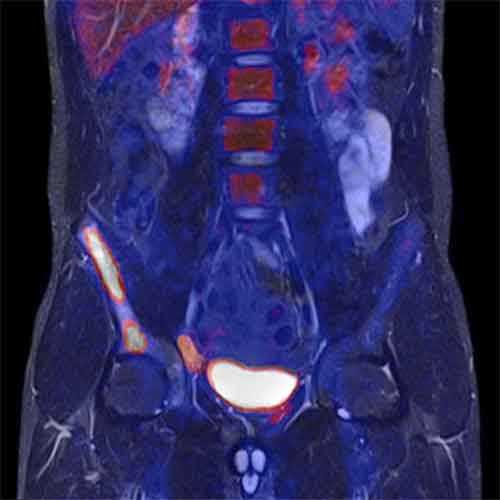

Il tomografo “offre infatti le informazioni della risonanza magnetica e della tomografia a emissione di positroni in un’unica immagine ad altissima risoluzione grazie all’innovativo sistema ibrido a 3 tesla. L’acquisizione in simultanea dei dati di entrambi gli esami fornisce un incremento nell’accuratezza diagnostica in campo oncologico, neurodegenerativo e cardiologico, consentendo una migliore individuazione della terapia ed una maggiore certezza sulla tipologia di intervento da eseguire (ad esempio, nel caso di una lesione tumorale, l’esame mMR indica la perfetta collocazione e dimensione della lesione, specificandone l’aggressività).

“La risonanza mMR – ricorda la Fondazione Sdn in una nota – è indicata soprattutto nello studio dei tumori dell’addome, i tumori della sfera genitale, del fegato e del tratto gastroenterico, ma è anche utile a livello encefalico sia nella patologia tumorale sia nella patologia neurodegenerativa, quale lo studio delle demenze”. (ADN KRONOS)